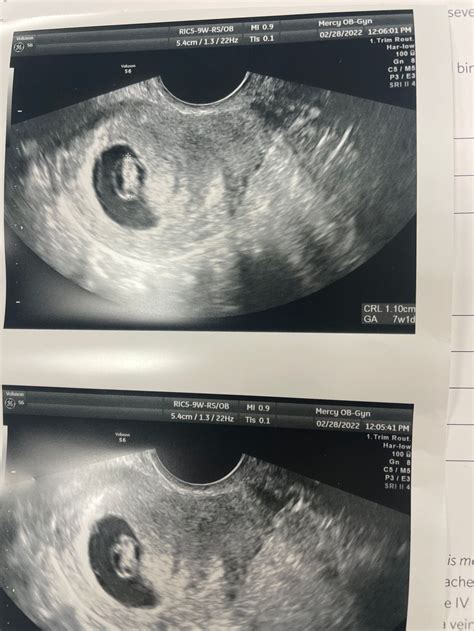

7 Week Ultrasound

The 7 week ultrasound is typically performed transvaginally, which involves inserting a probe into the vagina to get a clearer image of the uterus and the developing embryo. This method is particularly useful in the early stages of pregnancy when the embryo is still very small. The ultrasound can detect the gestational sac, yolk sac, and fetal pole, which are essential indicators of a healthy pregnancy.

It's important to note that the accuracy of the 7 week ultrasound can vary based on the equipment used and the skill of the sonographer. However, it remains a vital tool for monitoring the early stages of pregnancy.

• Images: The sonographer will take several images and measurements, which will be reviewed by your healthcare provider. You may be able to see the images on the screen during the procedure.

The results of the 7 week ultrasound provide valuable information about the health and development of the embryo. Here’s what the findings might indicate:

• Gestational Sac: The presence of a gestational sac confirms the pregnancy. The size and shape of the sac can indicate the gestational age and the health of the pregnancy.

• Yolk Sac: The yolk sac provides essential nutrients to the embryo. Its presence and size are crucial indicators of a healthy pregnancy.

• Fetal Pole: The fetal pole is the earliest visible part of the embryo. Its presence confirms the development of the fetus.

• Heartbeat: Detecting a heartbeat at 7 weeks is a positive sign, but it may be too early for some ultrasound machines. If a heartbeat is not detected, it does not necessarily indicate a problem.